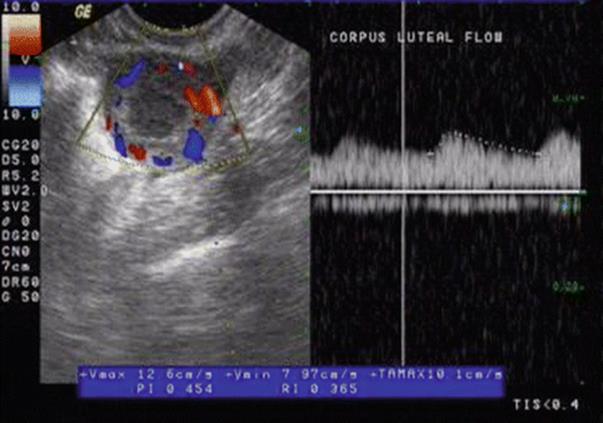

Doppler in the secretory phase gives an idea about the function of corpus luteum (CL). Usually, the RI of the corpus luteum (Fig. 2.15) is between 0.35 and 0.50. In luteal phase deficiency (LPD), RI is 0.58 ±0.04, PI is 0.70–0.80, and PSV is between 10 and 15.

Fig. 2.15

Doppler of corpus luteum

Luteal Phase Doppler

In the mid-luteal phase, the spiral artery RI is 0.48–0.52, uterine artery PI is 2.0–2.5, and uterine artery PSV is 15–20 (Fig. 2.16). Increased resistance to uterine blood flow in the mid-luteal phase is an important contributing factor in some cases of infertility. When pulsatility index (PI) is used as the measure of impedance, it was found that a PI of <3.0 [15] or <3.34 [16] was more favorable for pregnancy. No difference was found in uterine or ovarian artery PI between pregnant and non-pregnant women, but there was a non-significant increase in uterine receptivity when the uterine artery PI was in the range of 2.0–2.99 on the day of embryo transfer [17]. It was also seen that RI was found to be significantly lower at the time of oocyte collection in women who achieved a pregnancy [15]. In a recent study, Ng and colleagues [18] performed 3D ultrasound power Doppler 1 day after the LH surge in women undergoing frozen embryo transfer in natural or Clomiphene-induced cycles. These investigators found that endometrial thickness, endometrial volume, endometrial pattern, uterine PI, uterine RI, and endometrial and subendometrial 3D power Doppler flow indices were similar between the non-pregnant and pregnant groups [18]. They concluded that measurement of uterine artery blood flow should not be part of routine IVF practice. It was also emphasized in this study that the age of women was the only predictive factor for pregnancy. Early secretory transformation of endometrium is a feature of LPD [18].